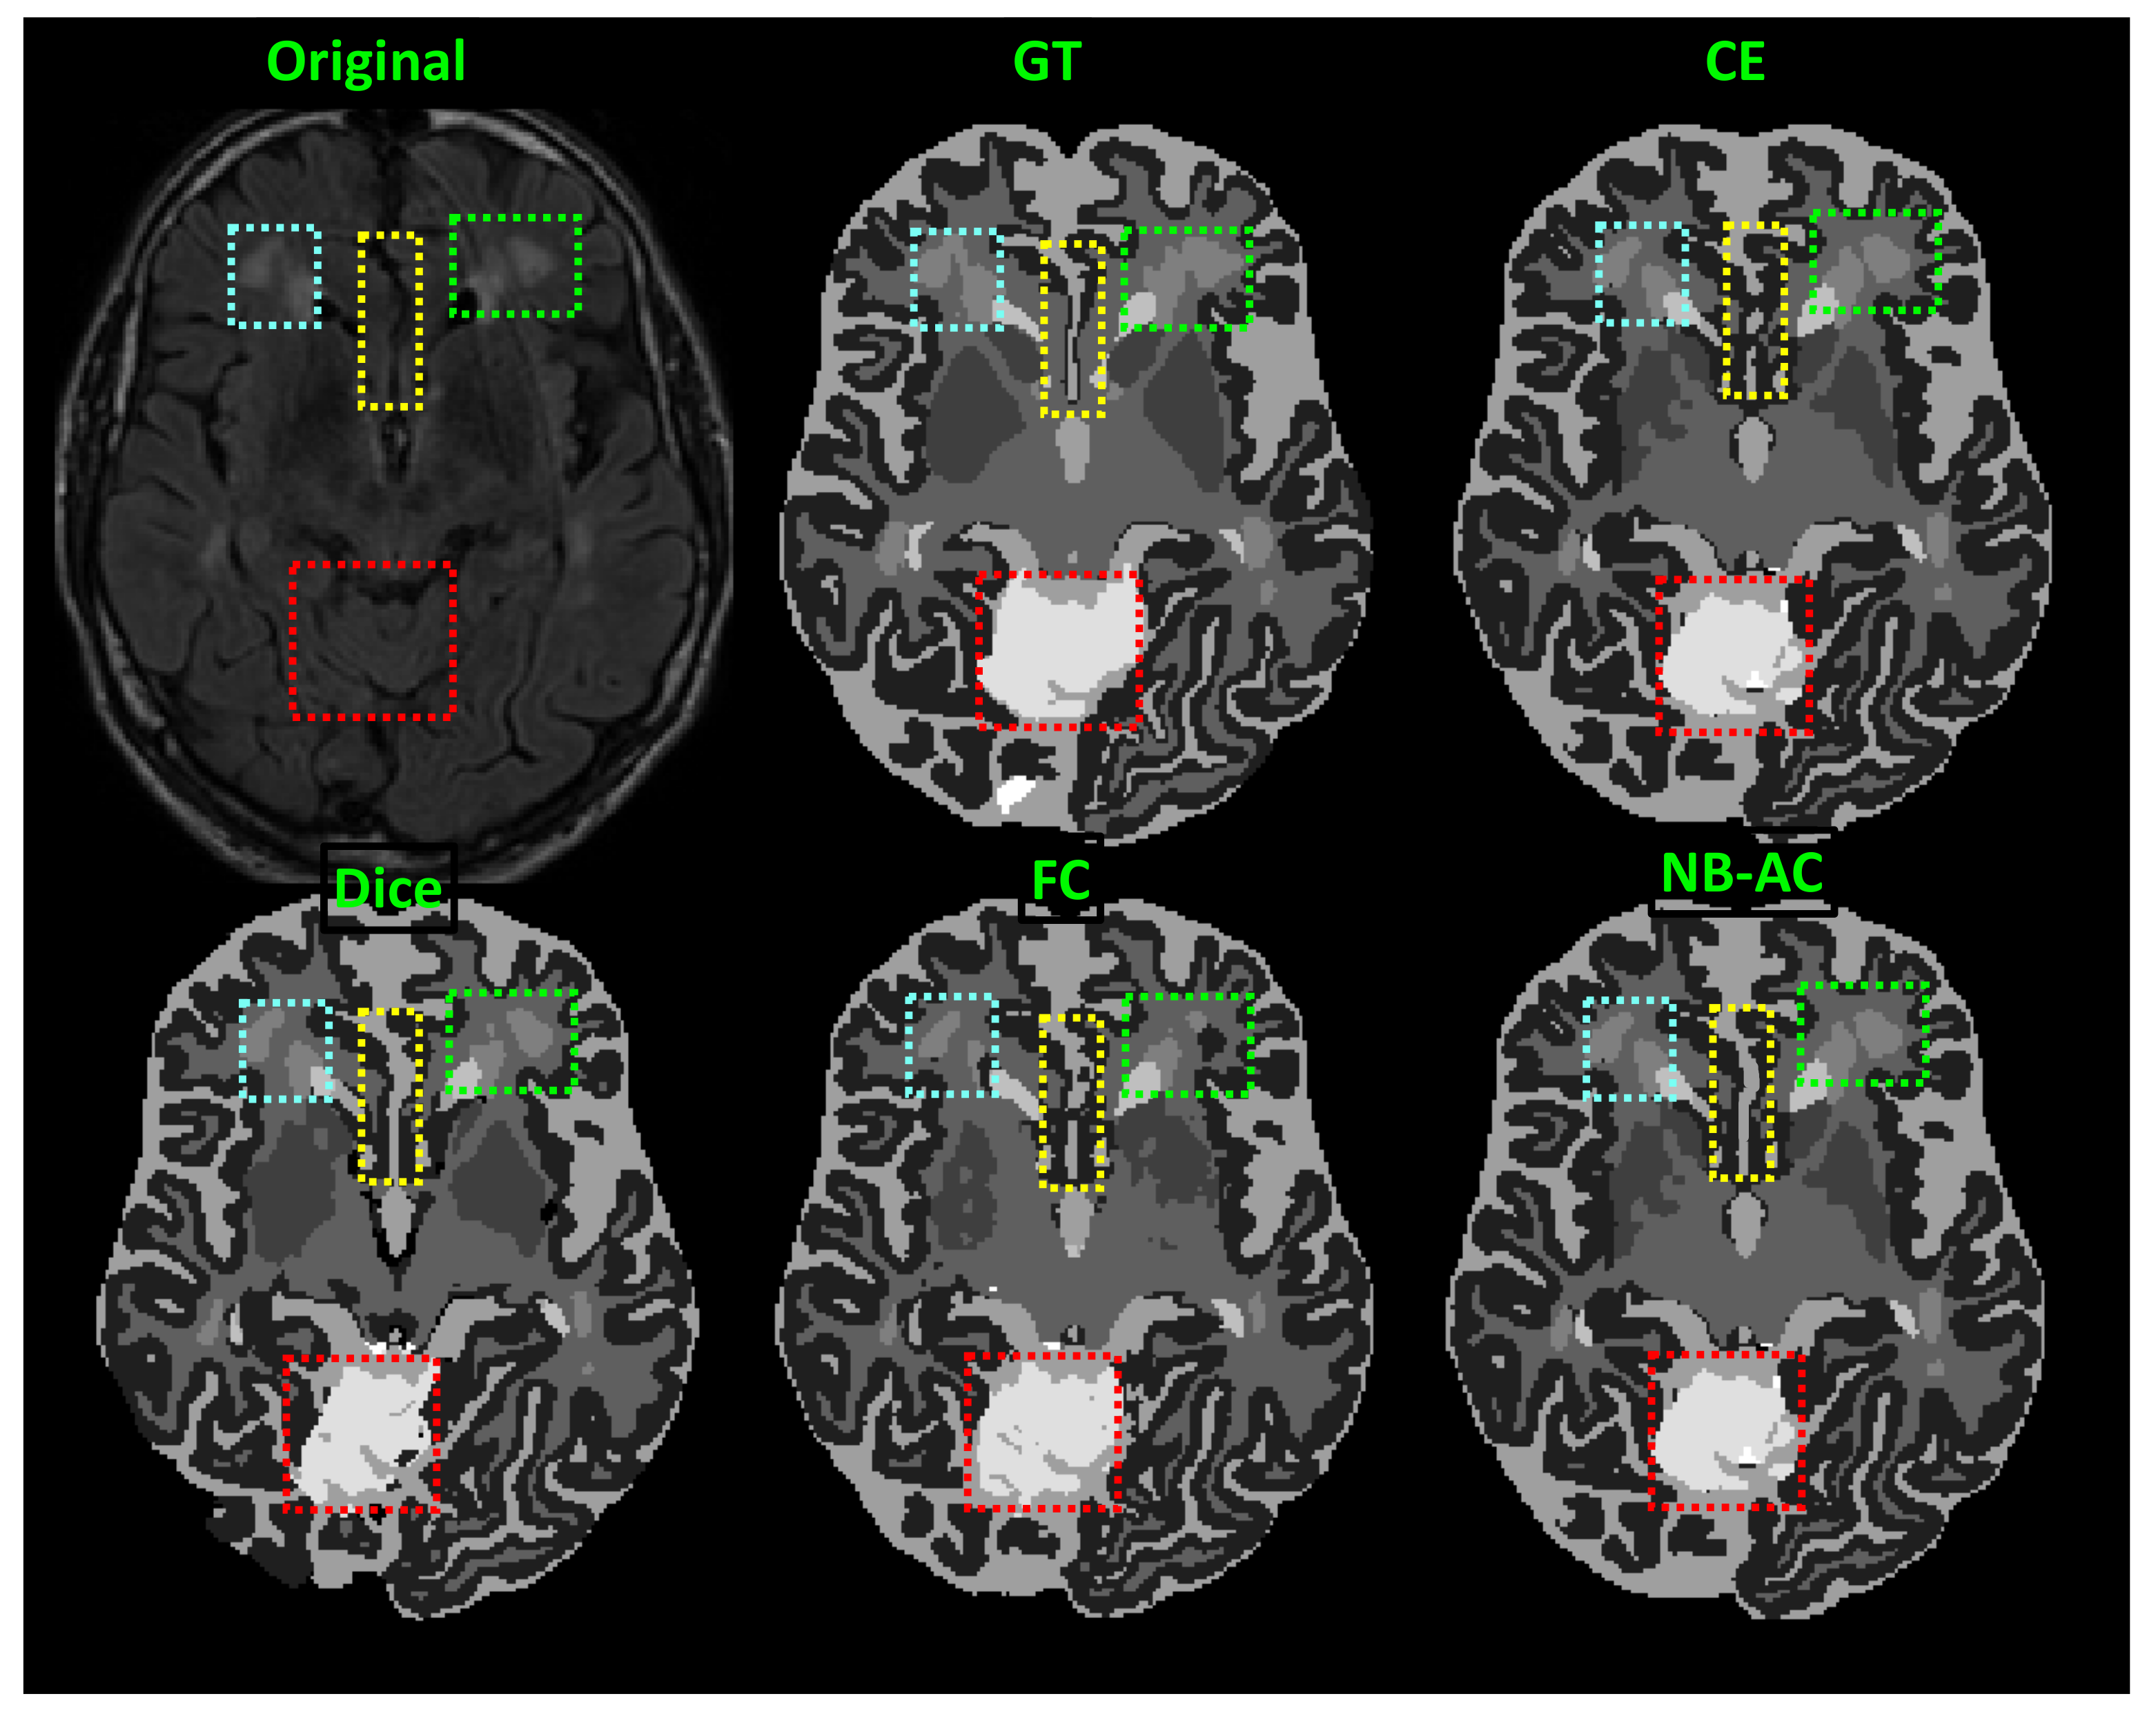

Figure 9.

Comparison between our results against other loss functions on the Unet framework. The image is from the MRBrainS 2018 dataset.

In Figure 8, the weak boundary vessel is highlighted in colored boxes. In such colored boxes, we can see the vessel is shown with poor contrast in the original image and the ground truth of the vessel is very thin. Far apart from other loss functions which are unable to capture such information, the proposed NB-AC has high capability to work in the case of weak object boundary segmentation. Not only for weak object boundary but also imbalanced-class data, Figure 9 and Figure 10 contain the performance of the middle slide of each image/volume that are from the MRBrainS 2018, BRATS 2018 datasets. In each figure, the colored boxes highlight areas corresponding to small class data and weak boundary object (especially the object boundary). Compared against other loss functions, our NB-AC loss obtains the closest result to the ground truth in both cases of weak boundary object and small object.

Clearly, comparing with the common segmentation losses, the proposed NB-AC loss improves the segmenting performance using the same network backbone. Take CE loss function as an example, the proposed NB-AC loss improved the segmentation accuracy regardless of the backbone networks (2D-FCN, 2D-Unet or 3D-Unet). Figure 8, Figure 9, Figure 10 and Figure 11 visualize the comparison between our loss and other loss functions. In these figures, some regions are highlighted to easily see the difference in segmentation results between loss functions.